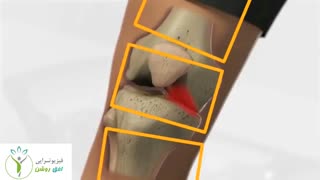

آرتروز زانو (knee osteoarthritis) یکی از بیماری های شایع بین مردم است که به دردهای شدید در ناحیه زانو منجر می گردد ( knee pain ) و باید درمان گردد. در صورت بی توجهی به آرتروز، این مشکل حادتر شده و به تعویض مفصل و جراحی منجر خواهد شد. روش های دارویی دارای عوارض سنگین بوده و درمان مناسبی نیستند. اما استفاده از حرکات ورزشی برای درمان آرتروز زانو بسیار موثر و کار آمد بوده و هیچ گونه عوارضی ندارد (knee osteoarthritis exercises).